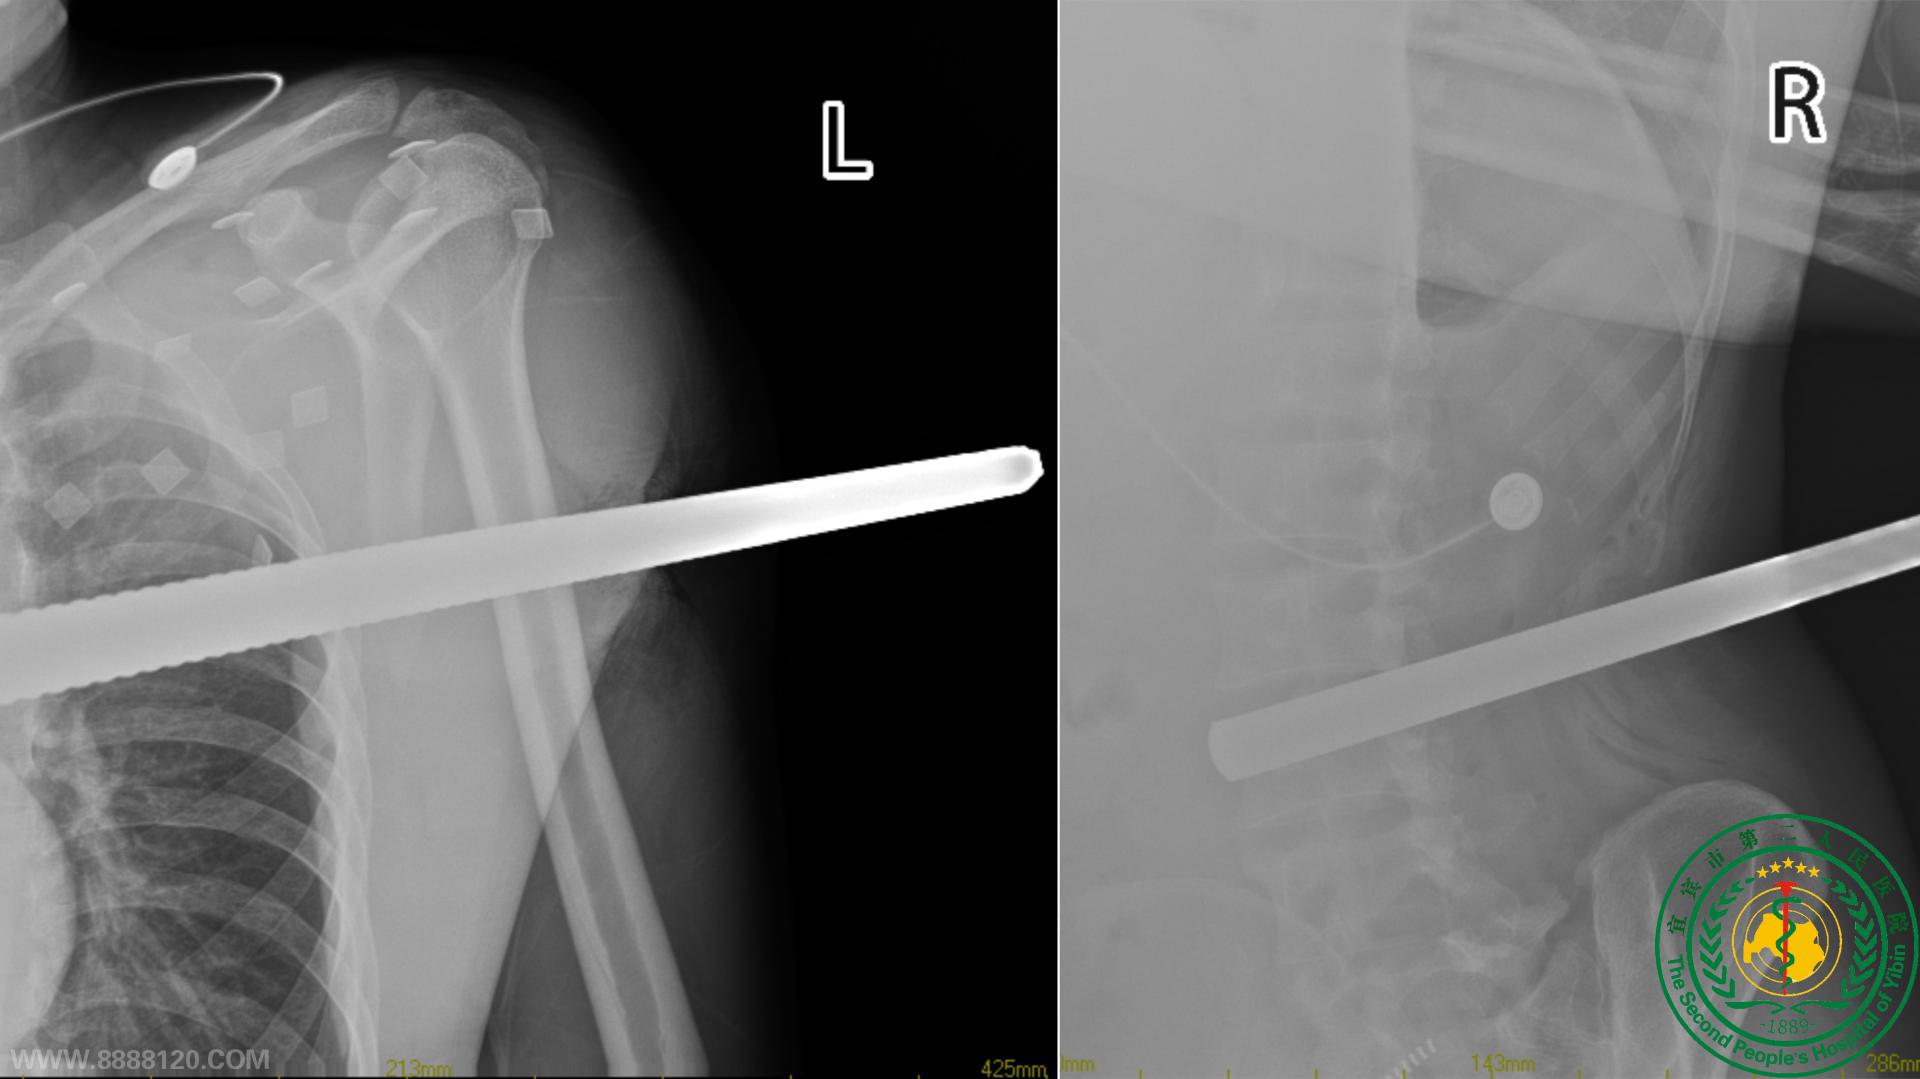

89日晚上,宜宾二院胃肠外科接诊了一名来自云南昭通永善县的36岁男子,当天下午该男子从2米高的建筑工地坠落,被2根直径约5cm的螺纹钢筋穿透腹部、左手臂等处,情况危急。

在医务人员提供保障的前提下,消防官兵速战速决,用液压剪先将男子身上的钢筋切断。随后胃肠外科、骨科、泌尿外科、麻醉科、ICU、放射科等科室联合协作,紧急会诊,制定抢救方案,历经过6个小时的紧急救治,插入该男子体内的2根钢筋被成功取出。目前,目前患者已脱离生命危险,由重症监护室转回普通病房。